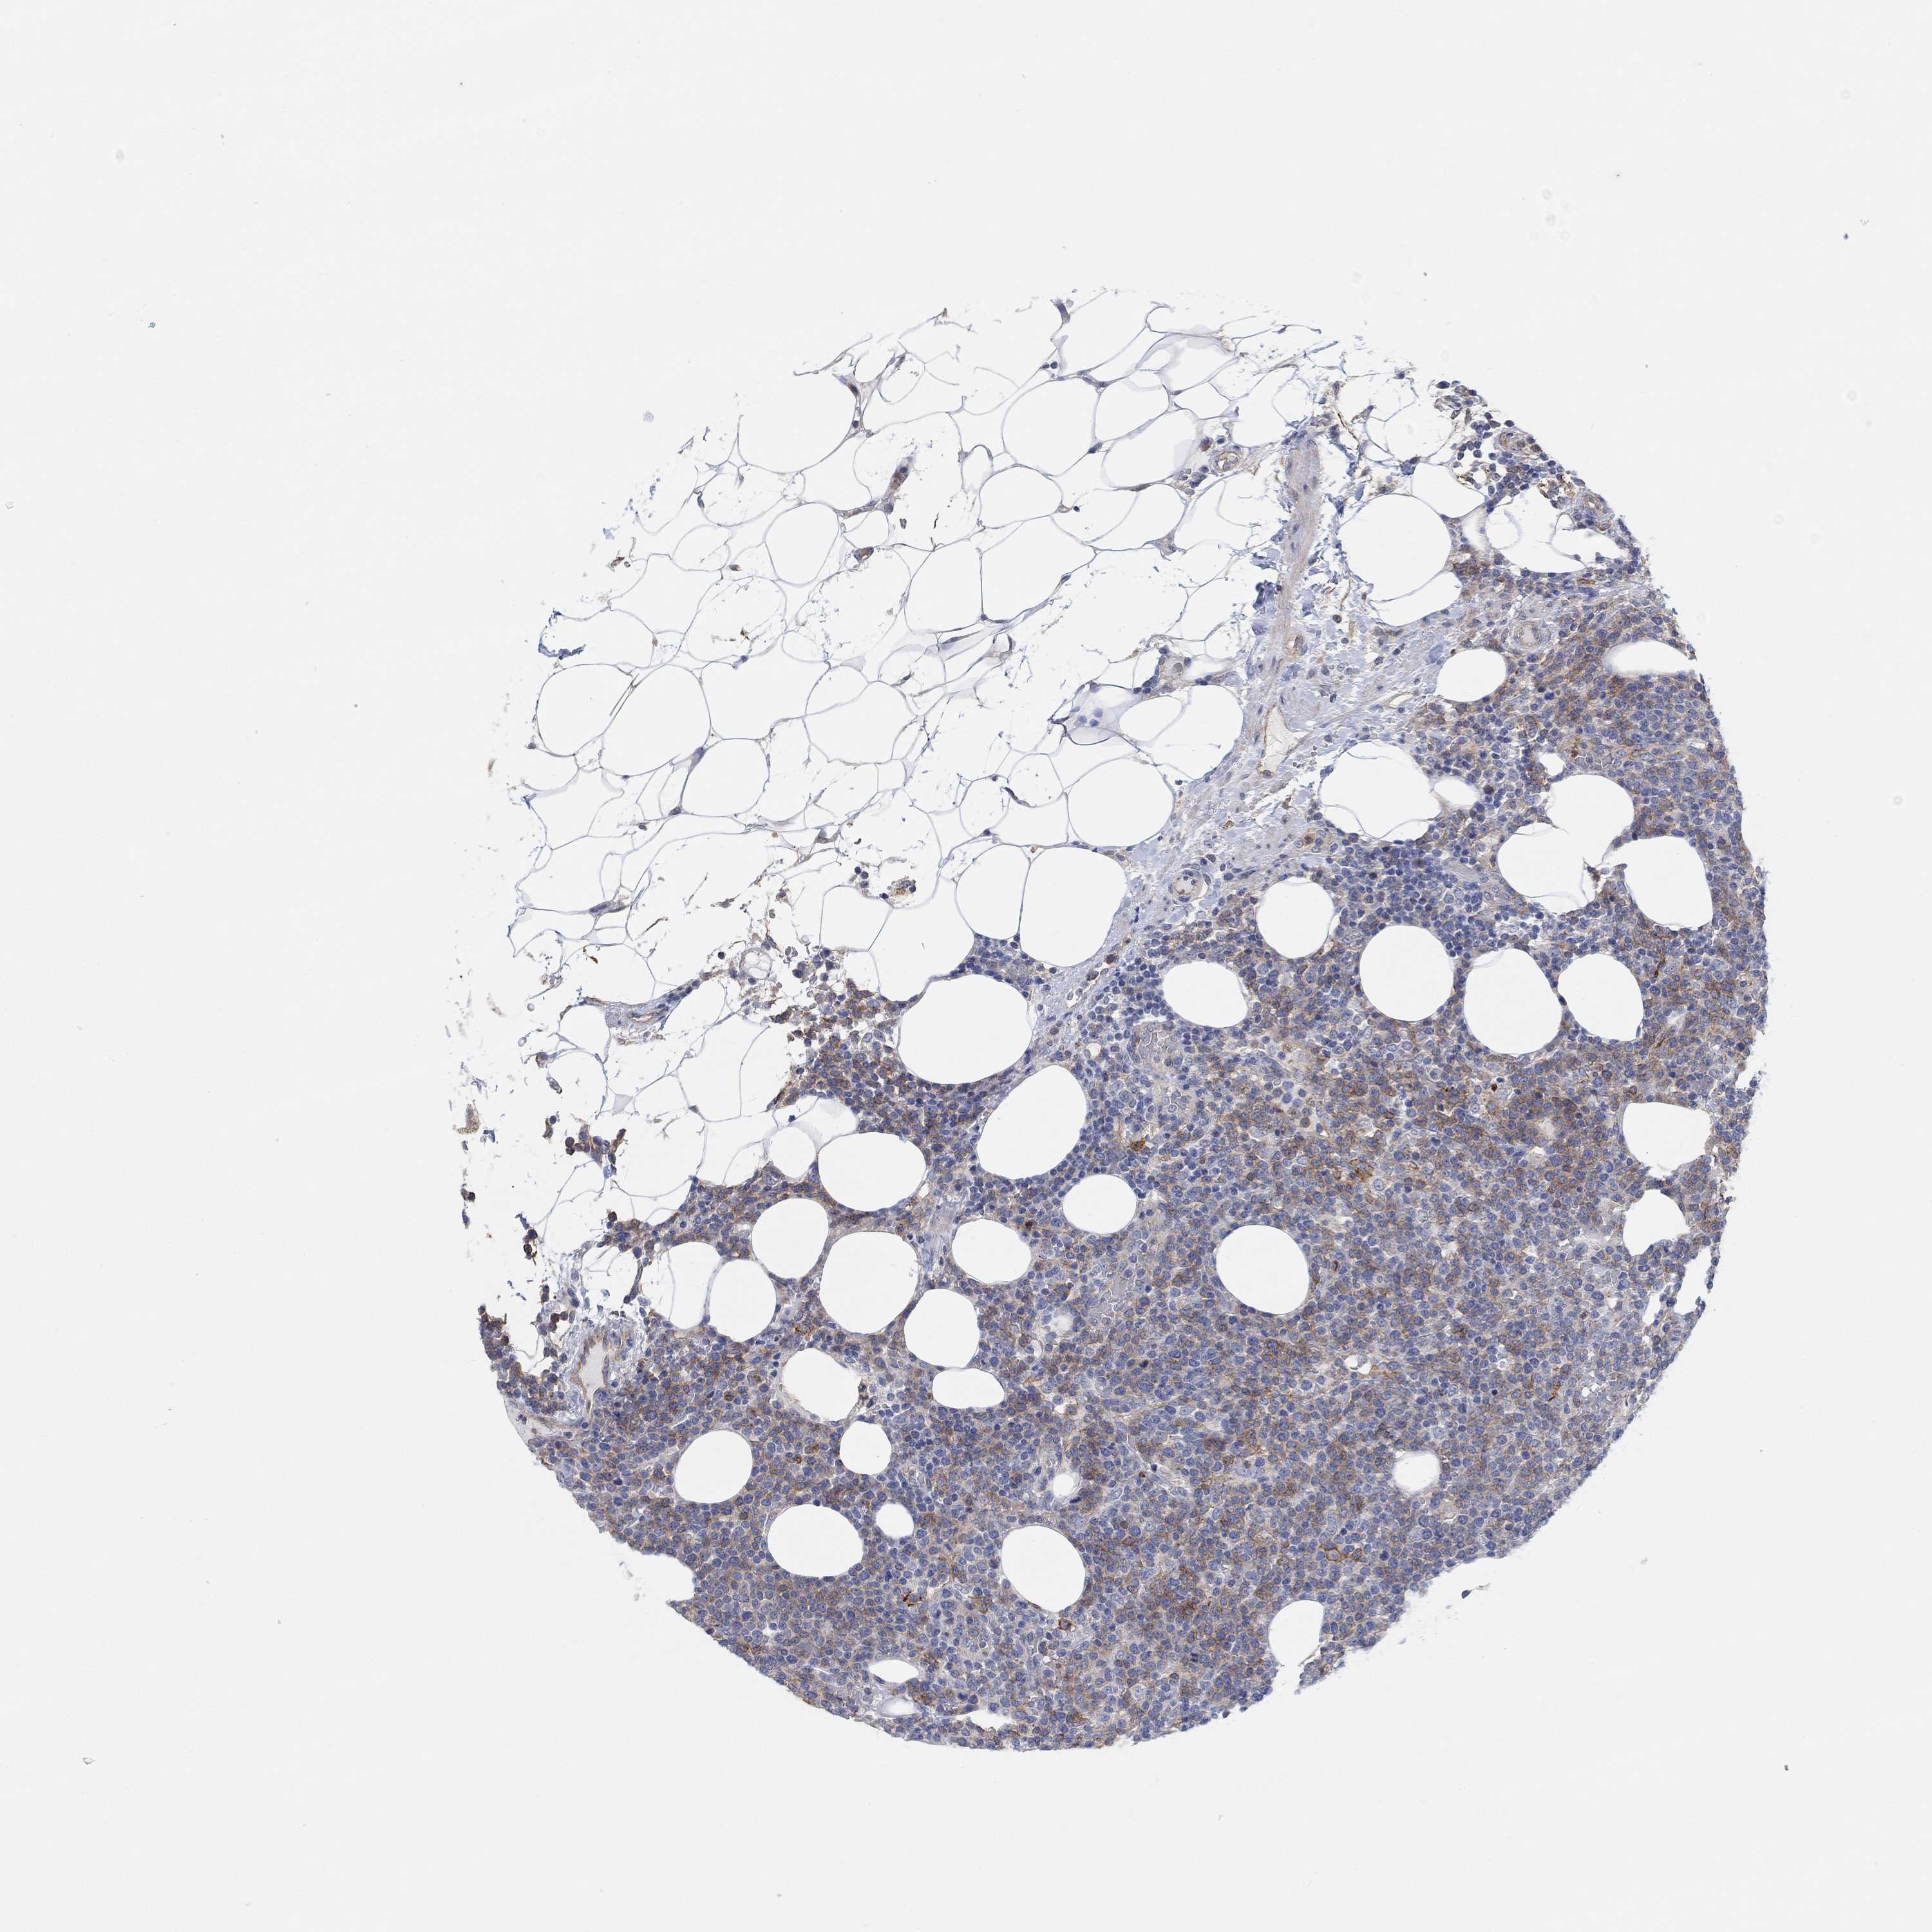

LYMPHOMA - Protein expressioni

A mouse-over function shows sample information and annotation data. Click on an image to view it in a full screen mode. Samples can be filtered based on level of antibody staining by selecting one or several of the following categories: high, medium, low and not detected. The assay and annotation is described here.

Antibody stainingi

Antibody staining in the annotated cell types in the current human tissue is reported as not detected, low, medium, or high, based on conventional immunohistochemistry profiling in selected tissues. This score is based on the combination of the staining intensity and fraction of stained cells.

Each image is clickable and will lead to virtual microscopy that enables deeper exploration of all samples and also displays staining intensity scores, fraction scores and subcellular localization as well as patient and tissue information for each sample.

Antibody HPA004199

Antibody HPA076871

Staining

High

Medium

Low

Not detected

Intensity

Strong

Moderate

Weak

Negative

Quantity

>75%

75%-25%

<25%

None

Location

Nuclear

Cytoplasmic/membranous

Cytoplasmic/membranous,nuclear

Malignant lymphoma, non-Hodgkin's type, High grade

Malignant lymphoma, non-Hodgkin's type, Low grade

Hodgkin's disease, NOS